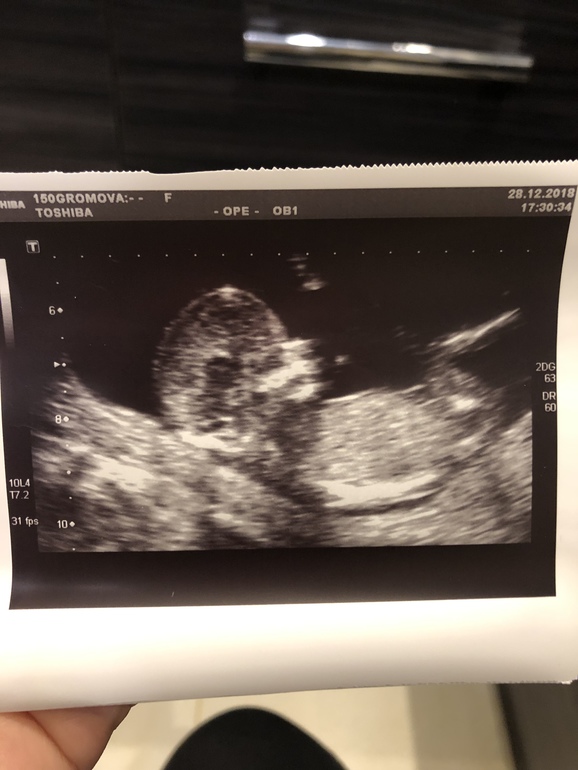

Пол малышаДевчули, кто понимает, скажите, ну похоже же на девочку? Я все ищу в интернете похожие снимки😄 врач сказала что мальчик, но я не верю, в 20 недель точнее будет видно, если я дотерплю😄

Вот эта беленькая черточка в районе ног, это же и есть половой бугорок?

Судя по этой картинке, то у меня девочка, так как на картинке бугорок прям стоит, а на моей фотографии параллелен позвоночнику. Но я что-то всего начиталась в интернете и думаю что нужно просто пойти через 3-4 недели на УЗИ. Тогда уже точно скажут.

Не хочу расстраивать, но у Вашей "девочки" коки видны... Специально фото увеличила, детально рассмотреть.🙊

Тут сомнительно пока. У меня со старшим сыном прям вверх пипка уверенно торчала, без сомнений было. Со вторым сыном были сомнения у врача, сейчас на 90% девочка, но половой бугорок смотрит вниз. Тут тоже вроде угол девчачий, но я почему-то в сомнениях, бугорок ли это.

Если бугорок, обведенный Вами кружочком и есть половой бугорок, то это девочковый пирожок. Пусть Ваши желания исполнятся.

По фото ощущение мальчика,но сами понимаете все вилами по воде,надо ещё подождать чтоб наверняка на УЗИ было видно